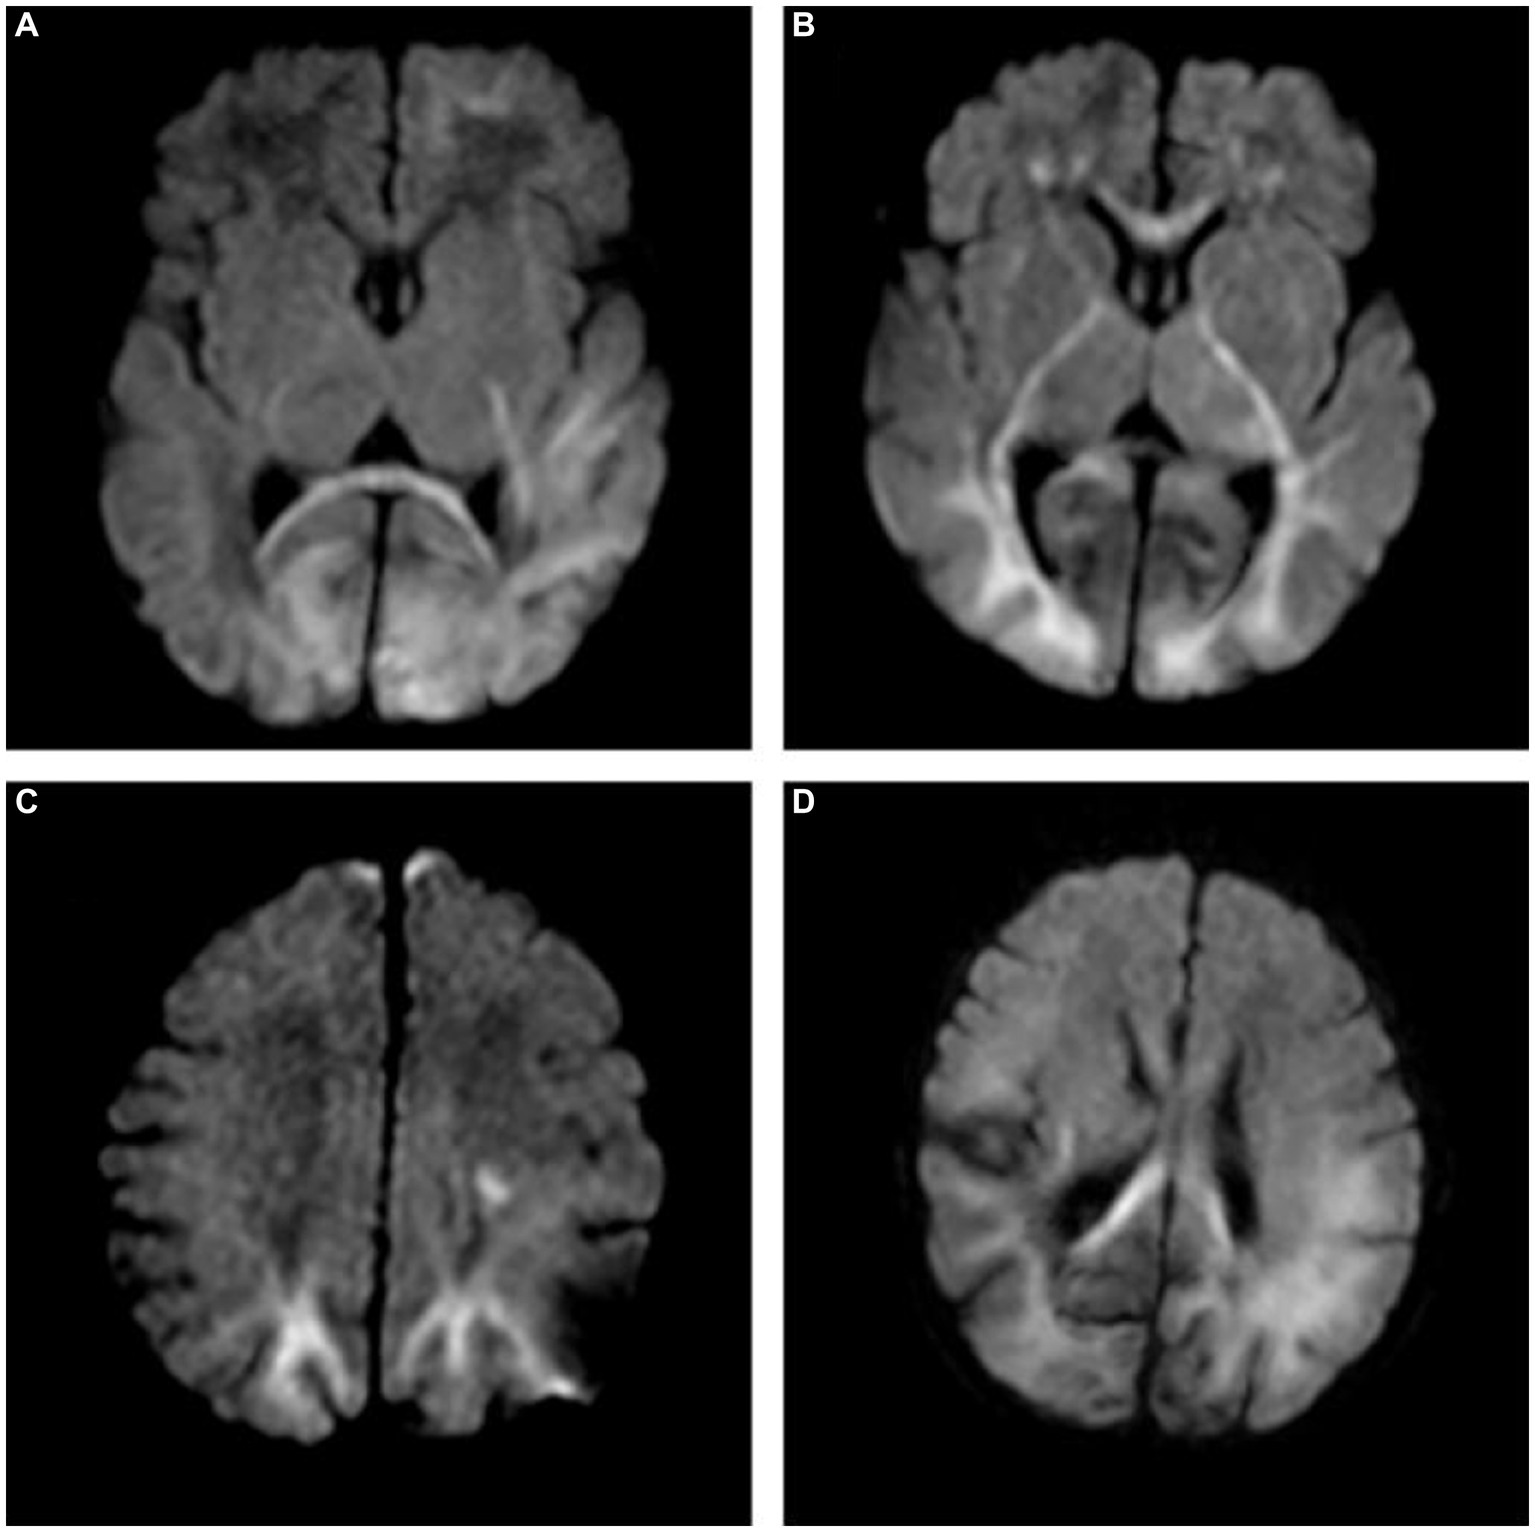

Figure 5

(A) A 7-day-old female neonate with HE, panel (A) diffusion-weighted imaging (DWI) revealed hyperintense lesions in the bilateral occipital lobe, the left frontal lobe, temporal lobe and the splenium of the corpus callosum, with the outcome of severe neurodevelopmental impairment, included in group B. (B,C) A 10-day-old male neonate with HE, panel (B) DWI revealed hyperintense lesions in the white matter of bilateral frontal lobe, occipital lobe, internal capsule, thalamus, and genu of the corpus callosum. (C) DWI revealed hyperintense lesions in the bilateral parietal lobe and centrum semiovale. (D) A 5-day-old female neonate with HE: DWI showed extensive lesions in the brain, included in group B.